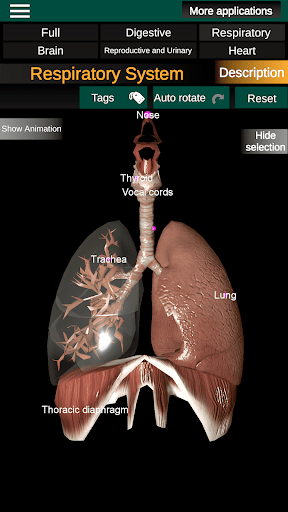

* Ademhalingssysteem, inclusief de luchtpijp, bronchiën, longen en een animatie van dit systeem.

* Gemakkelijk te openen en te navigeren (zoom, 3D-rotatie).

* Beschrijvingen van elk orgel.